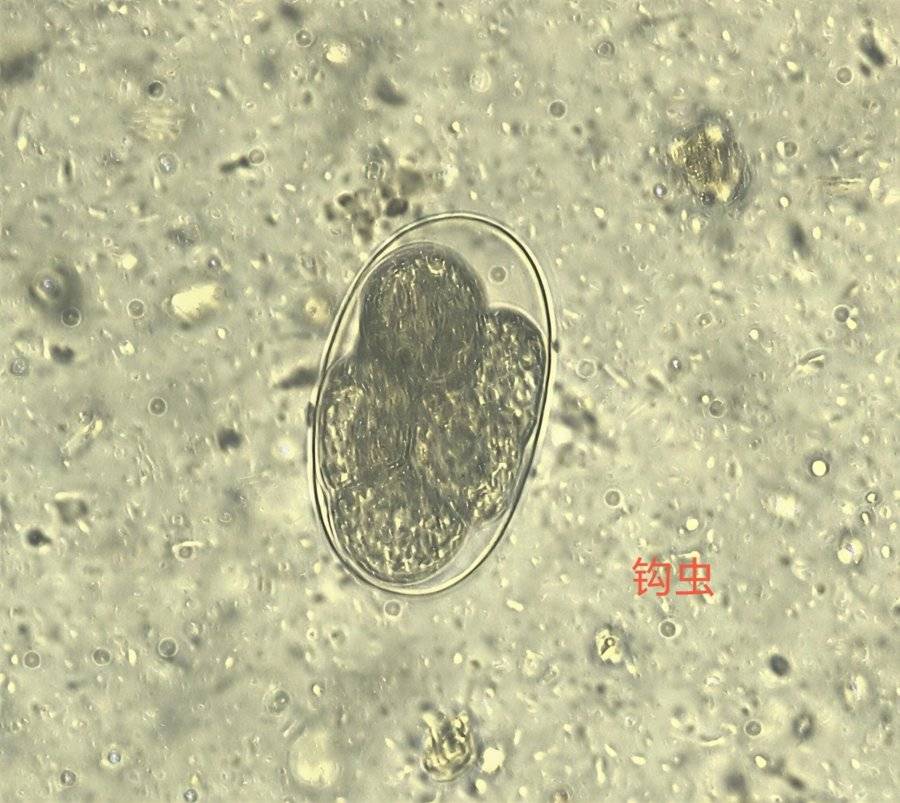

6号 Y6 钩虫卵

23号 S23 钩虫卵

钩虫卵是钩虫的繁殖阶段,通常呈椭圆形或卵圆形,大小约(56~76)×(35~40)微米,颜色无色至浅黄色,透明或半透明,卵壳薄且坚韧,其外观对称、两端圆钝,卵壳边缘间隙显著,表面可能光滑或有轻微凹凸感,部分种类卵壳上有小孔。

26号 S26 粪便中的“透明椭圆体”—钩虫卵

钩虫卵呈椭圆形,无色透明,卵壳薄,大小约(56-76)x(35-40)μm,随粪便排出时,卵内含4~8个卵细胞,卵壳和卵细胞之间有明显的空隙,预防钩虫感染的核心是阻断“皮肤接触感染”和“粪-口感染”,做好环境防护与个人卫生。

12号 S12 钩虫卵

钩虫卵:来自于一位贫血患者大便标本,400X,虫卵呈椭圆形,两端钝圆,卵壳极薄,内含数个卵细胞,排列呈桑葚状,卵壳与卵细胞有明显空隙。